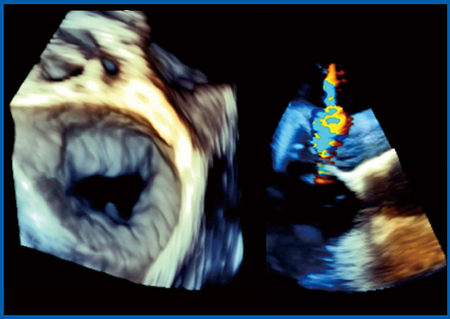

SHDの評価には,3D TEEが最適であると言われている。そこで,実際に,Aplio iシリーズに搭載された最新の3D TEEプローブで1例だけ撮像を行った。

図9は実際の画像であるが,僧帽弁が明瞭に描出されている。Bモードもきれいに描出されており,カラー3Dドプラも含めて,SHDの評価に十分な画像が得られている。さらには,僧帽弁解析ソフトウエアも登場しており(図10),東芝メディカルシステムズ社の3D TEE技術は大きく進化していると思われる。

図9 3D TEEによる僧帽弁の描出